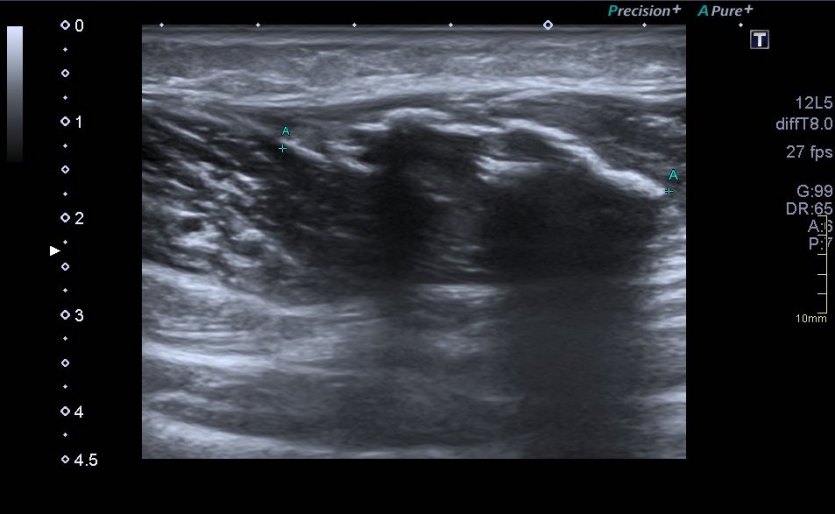

Lógicamente busco la comparación con el lado contralateral observando que es rigurosamente normal y hacemos foto comparativa para demostrar la patología. (Fig.3).Los cambios son muy evidentes.

Compruebo los hallazgos en ambos planos. (Fig 4).

Observa en el corte transverso de la misma región un Recto Anterior sano, ecográficamente perfecto, el de la figura 5,y compara con la imagen inmediatamente superior, figura 4, donde vemos el músculo retraído cambiado en su ecoestructura, edematoso en su contorno, con un aspecto claramente patológico.